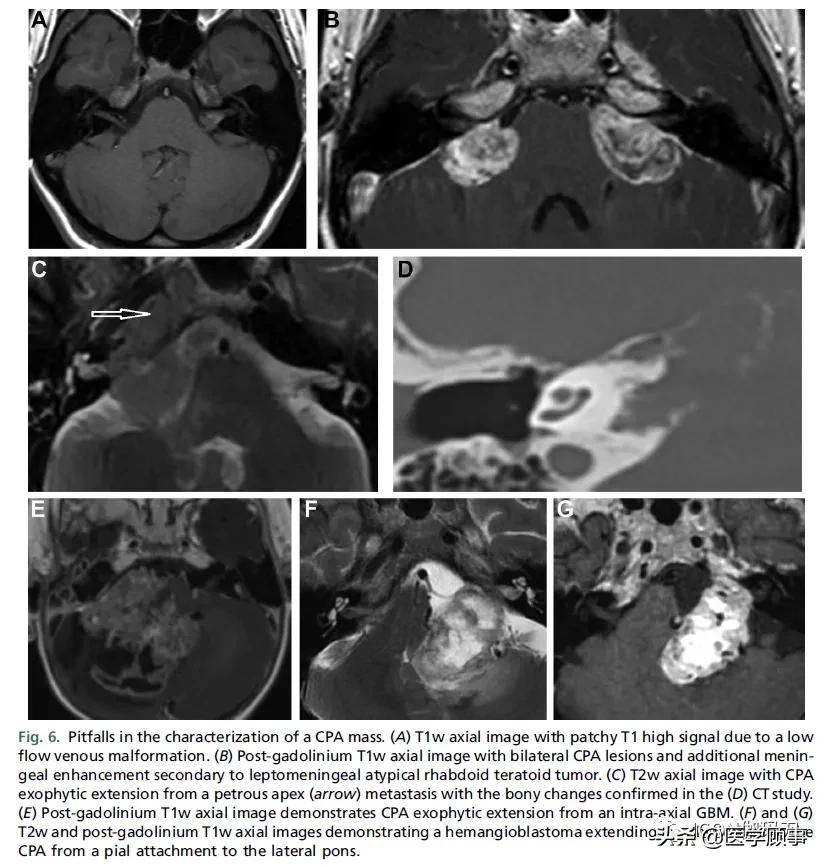

图6。CPA肿块表征的陷阱。(A)轴位T1w图像,由于低流量静脉畸形,斑块状T1高信号。(B)钆剂后T1w轴位图像,双侧CPA病变和继发于软脑膜不典型横纹肌畸胎瘤的额外的脑膜强化。(C) T2w轴位像,从岩尖(箭头)转移的CPA外生性扩展,伴 CT检查证实骨质改变(D)。(E)钆剂后T1w轴位像显示CPA来自轴内的胶质母细胞瘤(GBM)向外延伸。(F)和(G) T2w和钆剂后T1w轴位图像显示血管母细胞瘤外生性从桥脑侧方脑膜附着延伸到CPA。

当分析CPA肿块时,应确保它不是由邻近结构引起的。外生性轴内病变(Exophytic intra-axial lesions)从脑干和小脑延伸(如,儿童的髓母细胞瘤和转移性或成人的血管母细胞瘤)或从第四脑室(如室管膜瘤,脉络膜丛肿瘤)可能表现为CPA肿块性病变。值得注意的是,在年轻患者中,原发性CPA肿瘤很少见,因此在这种情况下,应始终考虑外生性轴内病变。同样,除非追溯到其起源点,起源于岩尖(如转移瘤或软骨肉瘤)或颈静脉孔(如副神经节瘤)的肿块可能被误认为CPA 的VS。